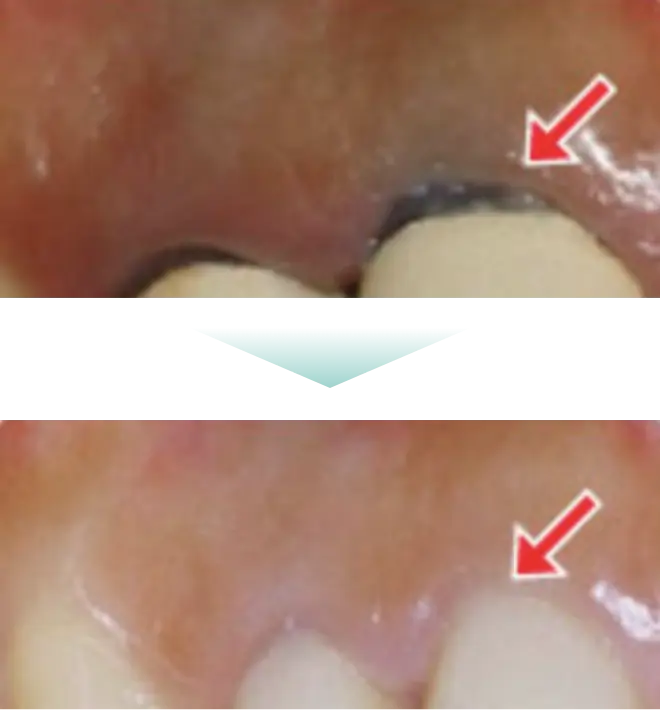

銀歯など金属イオンの溶出によって

歯や歯茎が黒ずむ心配もありません

通常は神経のない歯にいれるコア(土台) はハイブリッドと金属の芯を用いてメタルコア(土台)で作られます。ただこのメタルコアは金属のため錆びてしまったり、溶け出した成分で歯や歯ぐきが変色することがあります。

白色で光を透過するので、被せ物の白い歯も自然な透明感となります。金属を一切使用しないファイバーコアは金属アレルギーの心配もありません。このようにファイバーコアは歯とからだに優しい歯科治療の土台となる素材です。